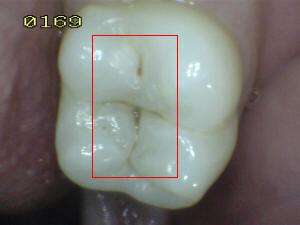

¿Determine los códigos pertinentes a cada imagen?

Click en el hipervínculo: Para comparar el resultado de su diagnóstico